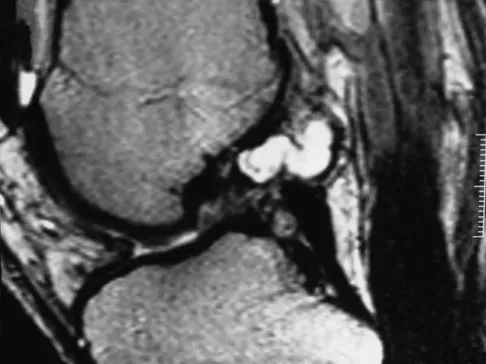

A 35-year-old woman who is a recreational runner reports posterior knee pain and tightness in the knee with flexion during running. She denies any history of trauma. Examination reveals normal patellar glide and tilt and no patellar apprehension. Range of motion is 5 degrees to 120 degrees, and quadriceps function and knee ligamentous examination are normal. Radiographs are normal. An MRI scan is shown in Figure 18. What is the most likely diagnosis?

Explanation